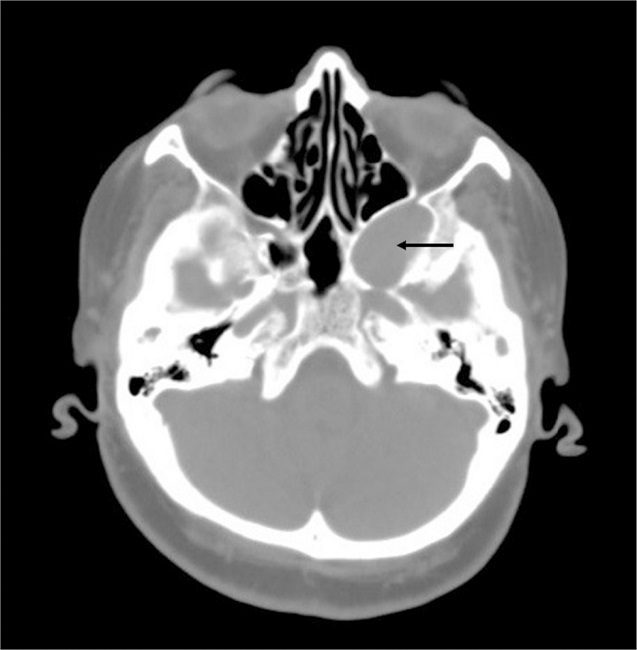

A 65-year-old female presented with headache and fullness on the face for several months. No other concomitant complaint was present. Nasal endoscopy, otological evaluation and cranial nerves examination were normal. Laboratory examination, complete blood count and routine blood chemistry were within the normal range. CT scan showed a well-circumscribed 3.4 cm × 2.8 cm soft tissue mass extending from the left pterygopalatine fossa to the left cavernous sinus (Fig. 1). It caused the remodeling in the posterolateral wall of the maxillary sinus, and the expansion at the cavernous sinus. Also, the mass is pushing the posterior wall of the maxillary sinus toward the anterior, and the lateral wall of the sphenoid sinus toward the medial.

Preoperative CT and MRI are useful in defining the location and extension of hemangiomas. CT findings of the cavernous hemangiomas are a soft-tissue density circumscribed mass, and also enhancing after injection of contrast. Hemangiomas of nasal cavity and paranasal sinuses may cause some changes on the adjacent bone. Generally, these changes seem like benign on imaging modalities. Dillon et al. reported three of six patients with cavernous hemangioma of nasal cavity have adjacent bone changes. In addition, all three cases have benign changes consisting of remodeling and expansion.5 On the other hand, hemangiomas demonstrate an iso or hypointense signal on T1-weighted MRI and an hyperintense signal on T2-weighted imaging. Also, these tumors show intense contrast enhancement.10